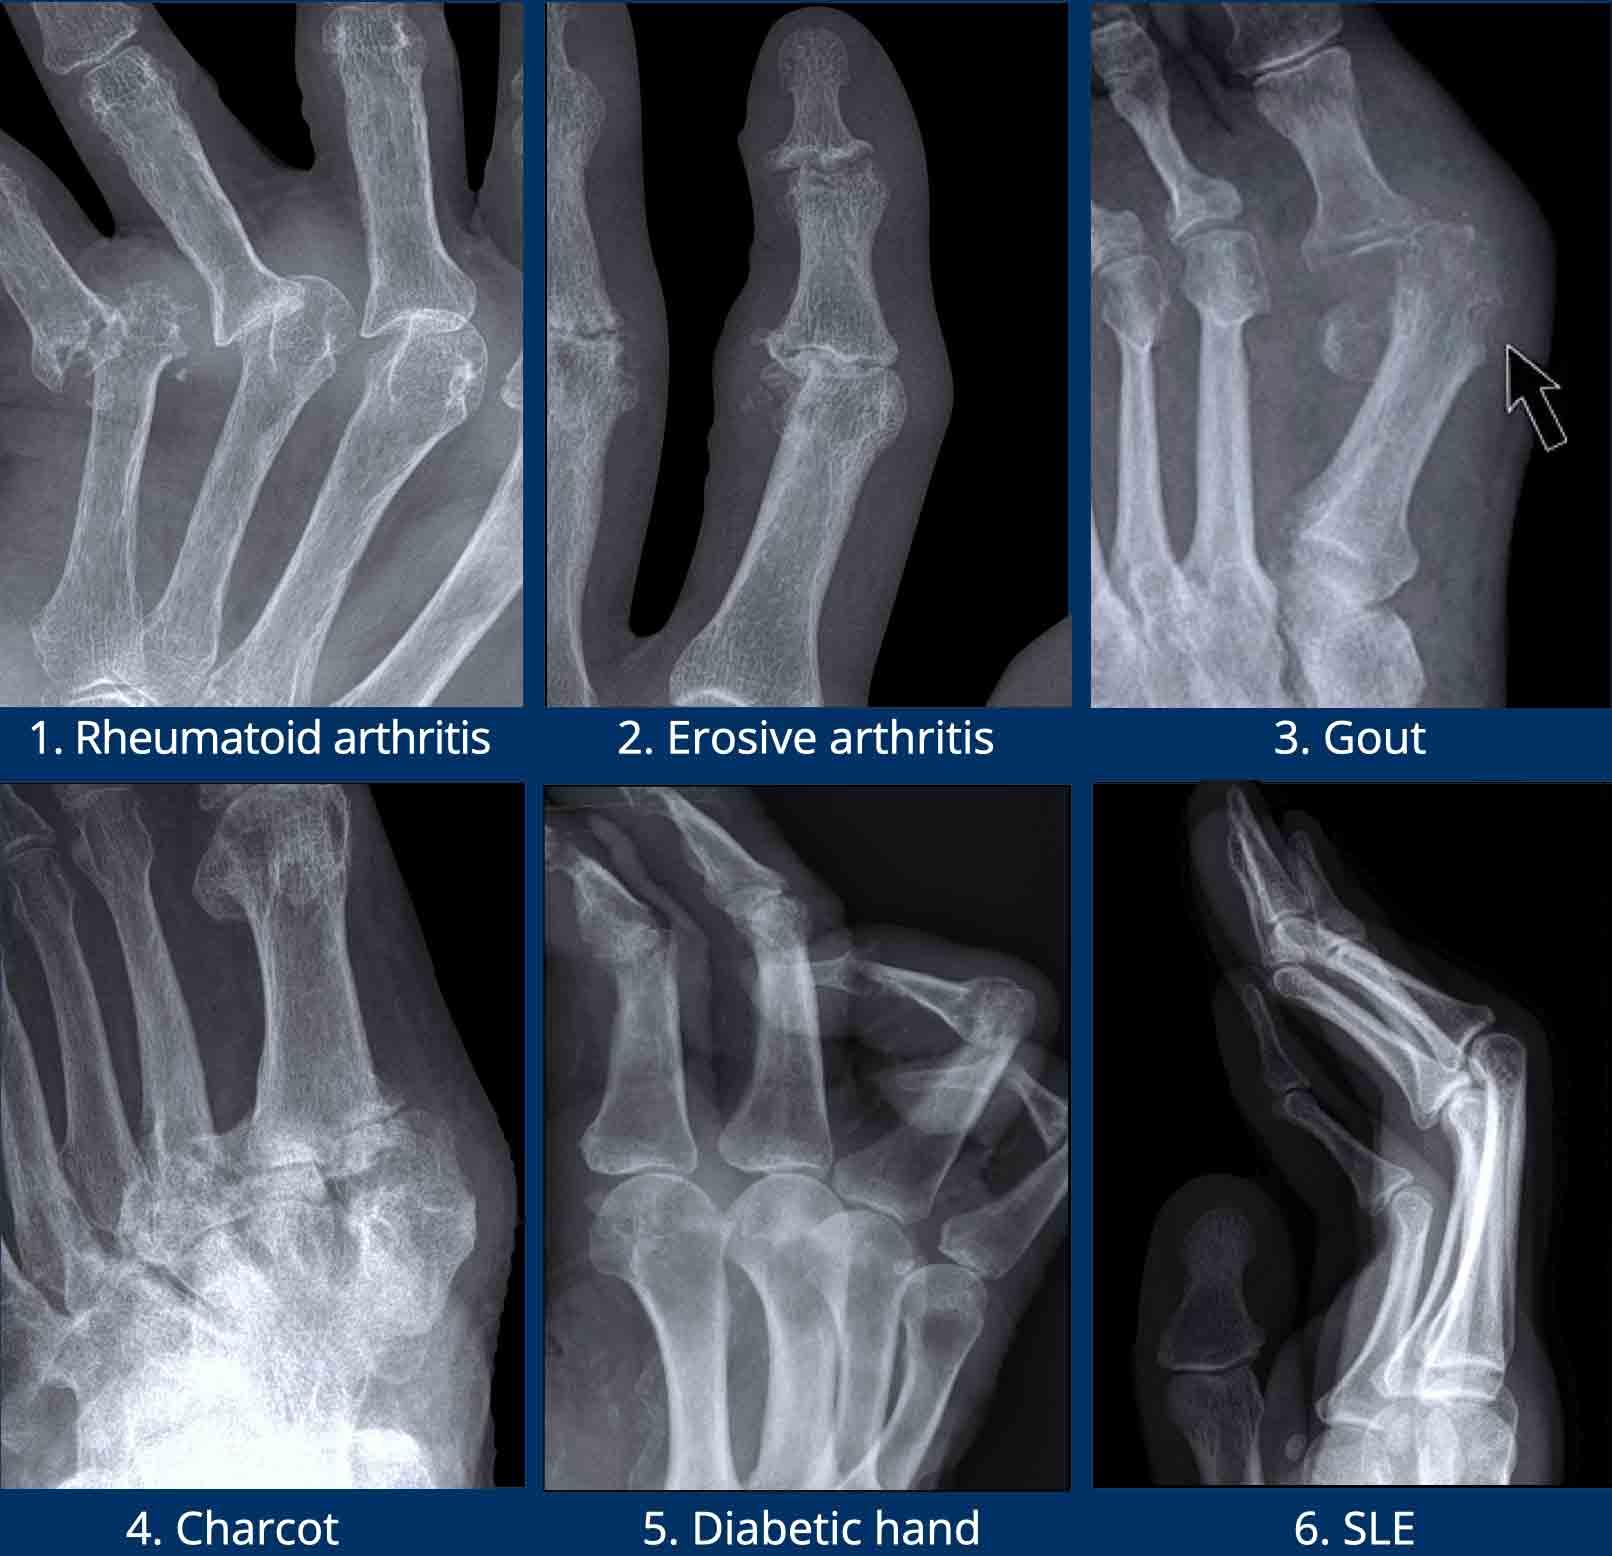

Các ví dụ điển hình về các dạng bào mòn đặc trưng

- Viêm khớp dạng thấp.

Bào mòn bờ khớp điển hình tại các khớp MCP. - Viêm xương khớp bào mòn.

Bào mòn xương dưới sụn tại các khớp DIP và PIP. Sự hình thành đồng thời của gai xương tạo ra biến dạng cánh hải âu. - Bệnh gout.

Bào mòn lệch tâm với bờ nhô ra. Bờ xơ cứng trong trường hợp này cho thấy bệnh mạn tính và tiến triển chậm. - Nhiễm trùng.

Tổn thương phá hủy kèm mất sụn và bào mòn xương. - Viêm khớp vảy nến.

Bào mòn xương thu hẹp đầu đốt ngón gần thành hình “bút chì”, tựa vào “cốc” được tạo bởi nền đốt ngón xa mở rộng do tăng sinh xương. - Xơ cứng bì.

Và các rối loạn đa hệ thống khác có thể gây bào mòn tại các chỏm đốt ngón xa, tình trạng này được gọi là tiêu xương đầu chi (acro-osteolysis).